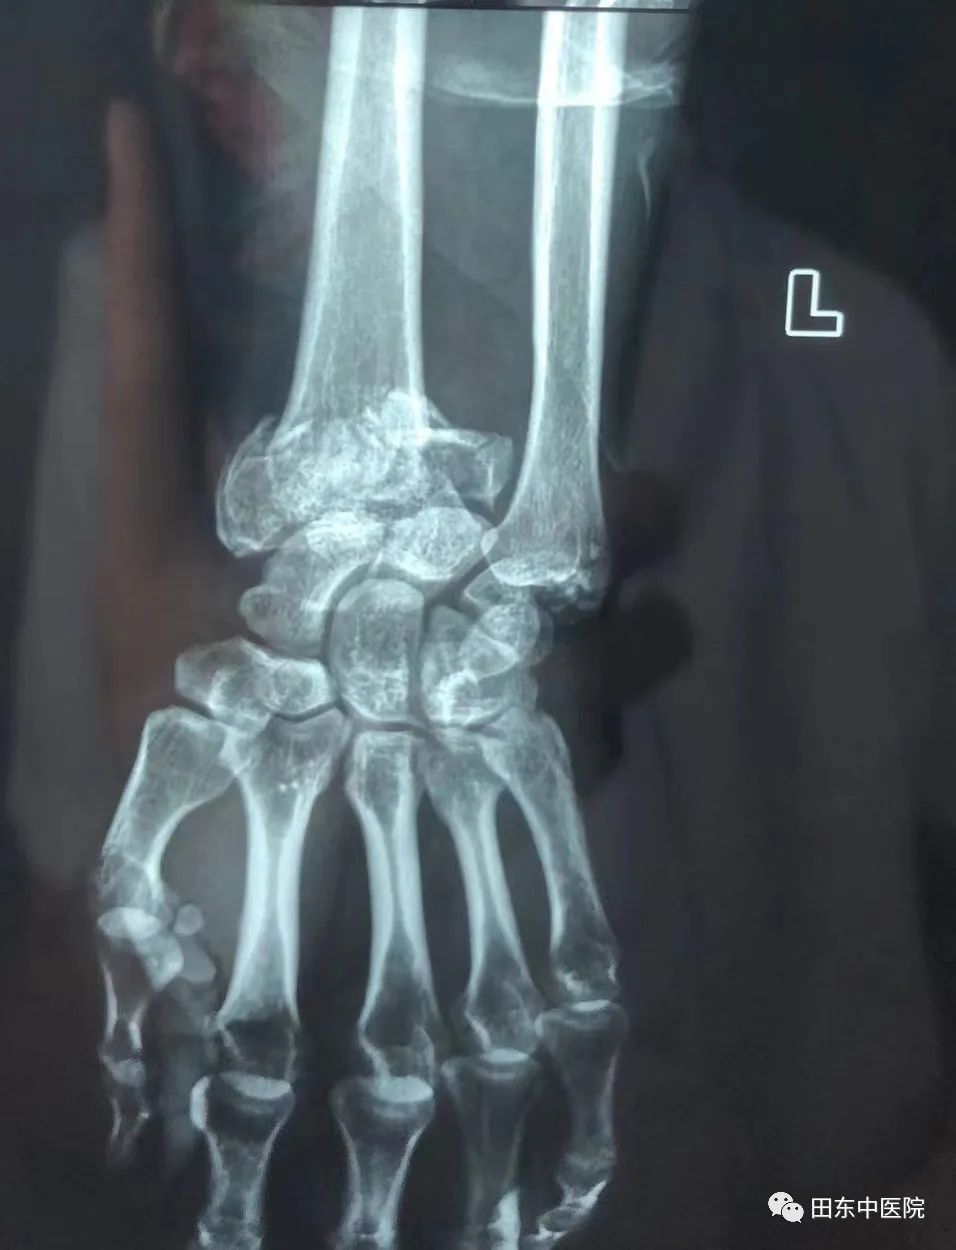

48岁的李叔(化名)从1.2米的施工凳子上不慎坠落导致左腕部肿胀、畸形,在家人的陪同下来到我院骨伤科就诊,经拍片检查后诊断为:左尺桡骨远端开放性骨折并尺桡腕关节半脱位。接诊的医生看过后,向骨伤科二区农达杰主任汇报病情,农主任决定为其行手法复位治疗。

▲左尺桡骨远端开放性骨折并尺桡腕关节半脱位